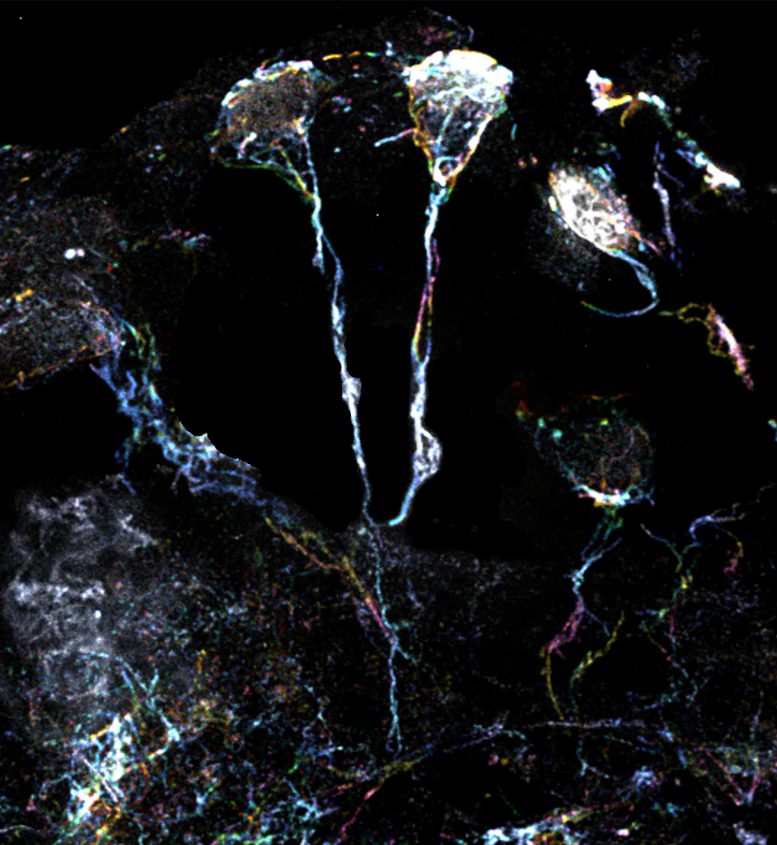

科學(xué)家團(tuán)隊(duì)使用放大倍數(shù)為10倍的超分辨率顯微鏡檢查了果蠅休眠神經(jīng)干細(xì)胞的標(biāo)志性微小纖維結(jié)構(gòu)。這些細(xì)微結(jié)構(gòu)的直徑約為1.5μm(比人類頭發(fā)的直徑小20倍),是從細(xì)胞體延伸出來的突起,富含肌動(dòng)蛋白或蛋白質(zhì)細(xì)絲。一種特定類型的Formin蛋白可以激活這些細(xì)絲并使其組裝。

果蠅大腦中處于休眠狀態(tài)的神經(jīng)干細(xì)胞具有富含肌動(dòng)蛋白絲的突起

果蠅大腦中處于休眠狀態(tài)的神經(jīng)干細(xì)胞具有富含肌動(dòng)蛋白絲的突起。圖片來源:杜克-新加坡國立大學(xué)醫(yī)學(xué)院